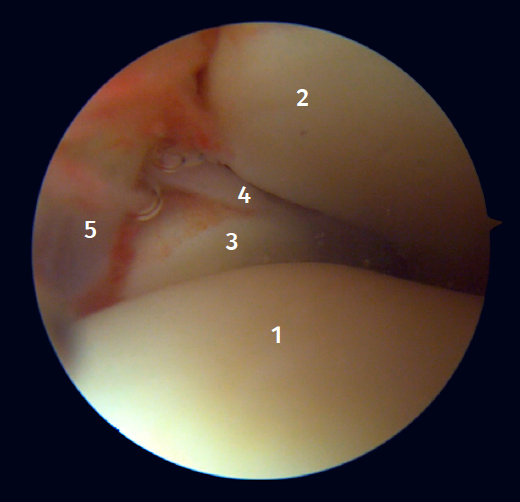

Arthroscopic anatomy of the medial complex

Arthroscopy allows us to see the deep fibers of the deltoid ligament, corresponding to the intra-articular portion of the ligament. Medial and proximal to the tip of the malleolus we have the insertion of the deep layer of the deltoid ligament. If there is no injury, we will see the anterior portion of the deep tibiotalar fibers. When injury is present, we can visualize the intermediate and posterior portion. The superficial bands, due to their more external location, are not visible by arthroscopy, unless there is no lesion of the deep bands (Figure 5).

Arthroscopic evaluation of the syndesmosis

From the anteromedial portal we can directly visualize the distal fibers of the ATFL. Disinsertion of these fibers does not always result in instability of the syndesmosis, but it does require us to check it. In our experience, we prefer assessment of the coronal plane of the syndesmosis. We introduce the arthroscope into the tibiotalar joint directing the camera cranially. In this way we have a direct view of the distal tibiofibular joint. We then assess stability by attempting to insert the palpation probe into the joint. If it is possible to do so, we classify the syndesmosis injury as unstable (Figure 6A).

Arthroscopic evaluation of the deltoid ligament

There are multiple methods for assessing instability of the medial complex; using the anterior ankle portals it is possible to assess the stability of the deltoid ligament in its main plane of action, corresponding to the coronal plane. Chun et al.(20) described instability when it is possible to introduce an arthroscopic palpation probe into the medial tibiotalar space (Figure 6B). Vega et al.(21) reported that, in the majority of injuries, the most anterior portion of the deltoid ligament is detached from the medial malleolus, while its proximal insertions remain intact. In this situation, the arthroscopic palpation probe can be inserted between the medial wall of the internal malleolus and the deep fibers of the deltoid ligament.

Figure 5. A: anterior view of the medial recess of the ankle; B: the fibers of the deep tibiotalar ligament are tightened with the palpation probe.

Figure 6. Maneuvers to demonstrate ligament instability. A: lesion of the syndesmosis allowing insertion of the palpation probe into the distal tibiofibular zone; B: lesion of the deltoid ligament allowing insertion of the probe into the medial tibiotalar space.